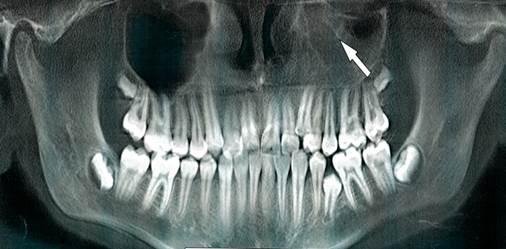

Рис. 1. Ортопантомограмма верхней и нижней челюстей. Стрелкой указано на пристеночное утолщение слизистой оболочки в правой верхнечелюстной пазухе.